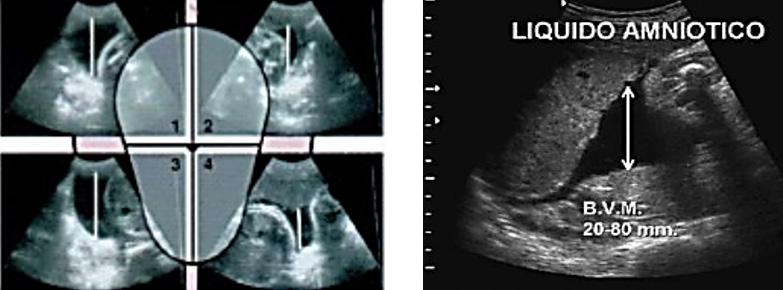

Líquido amniótico: Es un líquido claro, transparente con un pH de 7.4, el volumen tiene un carácter dinámico, 1000 ml a término. Su origen es mixto (materno – fetal). En las primeras 20 semanas, constituye un ultrafiltrado del plasma materno por trasudado (líquido isotónico); posteriormente, la fuente principal es la orina fetal (líquido hipotónico). La principal forma de eliminación es a través de la deglución fetal (60%). Sus funciones son diversas: protección, crecimiento fetal simétrico, efecto antibacteriano, termorreguladora, papel primordial en el desarrollo del pulmón fetal.

La ecografía del III trimestre (30-34 semanas) valora el crecimiento fetal (talla y peso), la localización de la placenta y el volumen del líquido amniótico.